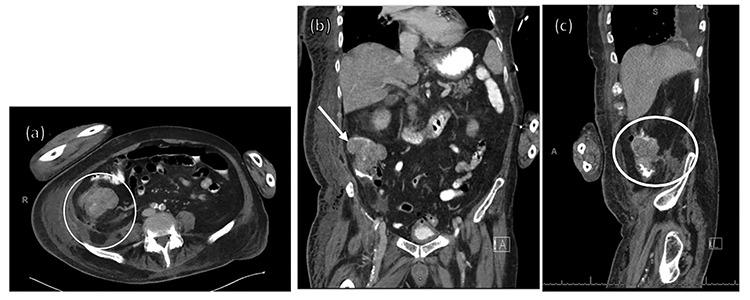

一例继发于盲肠癌穿孔的坏死性筋膜炎非典型病例。

An atypical case of necrotizing fasciitis secondary to perforated cecal cancer.

Necrotizing fasciitis is an aggressive, life threatening soft tissue infection that requires high index of suspicion for diagnosis. Diagnosis is clinical with management including broad spectrum antibiotics and emergent operative debridement. The majority of cases are secondary to underlying medical processes, local tissue damage, abscess, or inciting procedure, with a paucity of data correlating causation with colon cancer. We describe the case of an 84-year-old man presenting with sepsis of unknown origin who was diagnosed with an atypical presentation of necrotizing fasciitis secondary to a perforated cecal malignancy. His case is unique in that a less virulent polymicrobial infection was likely involved as he initially improved with conservative management alone. He ultimately declined and expired secondary to overwhelming sepsis from his infection. This case highlights the importance of maintaining a high index of suspicion for necrotizing infection and considerations for alternative etiologies of infection including perforated malignancies.

摘要

坏死性筋膜炎是一种侵袭性、危及生命的软组织感染,诊断时需要高度怀疑。诊断依靠临床判断,治疗包括使用广谱抗生素和紧急手术清创。大多数病例继发于潜在的医疗过程、局部组织损伤、脓肿或诱发手术,与结肠癌相关的病因数据较少。我们描述了一名84岁男性患者的病例,该患者出现不明原因的败血症,被诊断为盲肠恶性肿瘤穿孔继发的坏死性筋膜炎非典型表现。他的病例独特之处在于,可能涉及毒性较低的混合微生物感染,因为他最初仅通过保守治疗就有所好转。他最终病情恶化,因感染导致的严重败血症而死亡。该病例强调了对坏死性感染保持高度怀疑的重要性,以及对包括恶性肿瘤穿孔在内的感染替代病因的考虑。